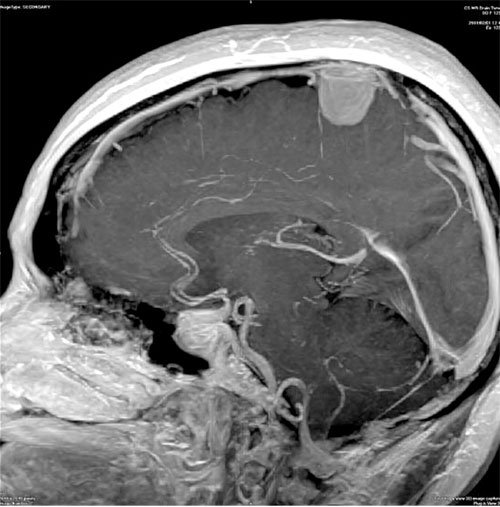

Η νανοκάψουλα που θα μεταφέρει το αντικαρκινικό φάρμακο, ίσως είναι η λύση για τις περιπτώσεις που τα συμβατικά φάρμακα δεν μπορούν να εισχωρήσουν σε όλα τα σημεία του εγκεφάλου.

Το εγκεφαλικό «φράγμα αίματος» είναι ένας φυσικός μηχανισμός που ουσιαστικά προστατεύει τον ευαίσθητο εγκέφαλο από τοξικά μόρια που κυκλοφορούν στο αίμα. Ο μηχανισμός αυτός όμως είναι ο ίδιος που δεν αφήνει τα χημικά να κτυπήσουν και τους όγκους που δημιουργούνται.

Οι επιστήμονες του κέντρου μοριακής ιατρικής Max-Delbruck της Γερμανίας, έχουν κατασκευάσει μια νανοκάψουλα η οποία περιέχει το αντικαρκινικό φάρμακο, πάνω στην οποία έχει εφαρμοστεί ένα μόριο το οποίο απορροφάται από φράγμα αφού αναγνωρίζεται ως ωφέλιμο!